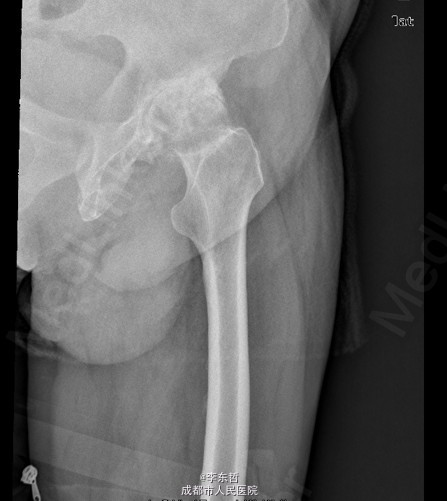

患者男,76岁,因“外伤致左髋部疼痛40多年,加重伴跛行2年”入院;患者自诉40多年前因一次摔伤致左髋关节脱位,给予手法复位后治愈,以后时有疼痛,关节活动好,不影响行走,4年前出现左髋部疼痛加重,活动后明显,休息后缓解,无腰腿痛,无肢体麻木等不适,给予对症治疗,稍有好转,以后反复发作,长时间行走后疼痛明显加重,2年前出现左下肢无力,长距离行走后出现跛行,且左髋关节有异响感;2月前出现左髋部疼痛加重,行走时尤为明显,步行约500米即出现疼痛,伴跛行,偶有静息痛;以后反复出现左髋部疼痛,并逐渐加重,严重影响日常生活;1月前于当地医院摄片提示左股骨头坏死,为求进一步治疗,遂来我院,门诊以“左髋骨关节炎”收入住院。 患者自患病以来精神、饮食、睡眠可,二便正常,体重无明显变化。

查体:左侧腹股沟中点深压痛,左髋部伴有轴向叩击痛,双下肢感觉正常,双足背动脉搏动良好。左下肢较右下肢短缩约2cm;左髋屈65°,伸0°,内收10°,外展20°,内旋5°,外旋10°,左髋活动受限,内外旋诱发疼痛;Thommas征阴性,“4”字试验阳性;左下肢肌力正常,活动良好,右侧正常 ;辅助检查:X片示:左侧股骨头塌陷、密度增高,股骨头坏死可能,左髋骨质疏松.。